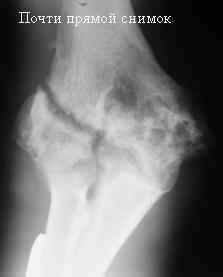

Стойкая комбинированная контрактура правого локтевого сустава

Увжаемые коллеги! На консультации больной со стойкой комбинированной контрактурой правого локтевого сустава.

В прошлом - спортсмен, сейчас охранник. Травма 2 августа 2008г., автодорожная. Оперирован в одной из больниц города. Остеосинтез, два месяца гипс. Объем движений с тех пор не изменился. Боли после физнагрузки (пытается тренироваться).